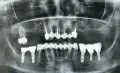

Был сделан контрольный снимок до лечения и после лечения. На снимке, сделанном после лечения, я увидела, что много пломбировочного материала вышло за пределы верхушки корневого канала.

На снимке видно, что один из каналов заполнен не до конца. Я задала вопросы врачу и получила ответ, что все в порядке, работа выполнена правильно и ничего страшного в том, что пломбировочный материал вышел за пределы канала.